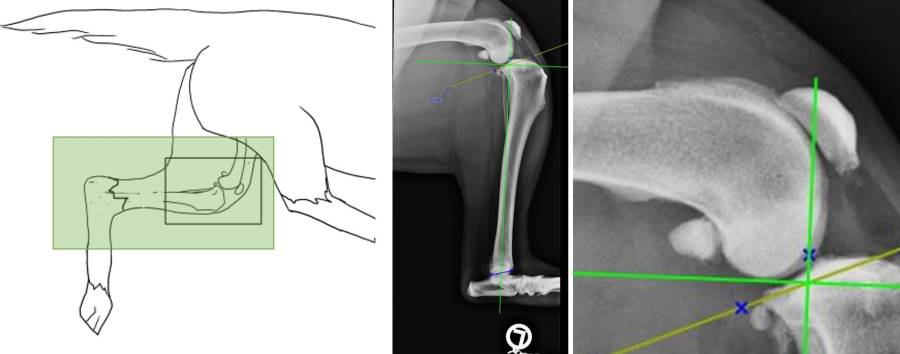

Röntgen prä-OP TPLO